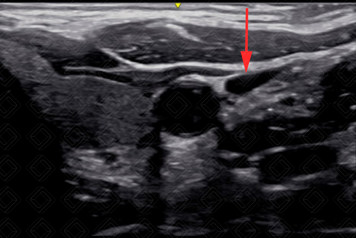

6. Avaliar compressibilidade do vaso (diferenciar artéria de veia) (Figura 3).

Texto alternativo para a imagem Figura 3. Veia jugular interna após compressão com transdutor (seta vermelha). Créditos: Dr. Igor Biscotto - Rio de Janeiro/RJ.